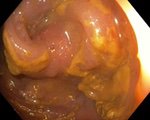

Мелкие полипы ободочной кишки.

В слепой кишке – полип диаметром 0,2см, гиперпластического вида.

В с/з восходящей кишки имеются 4 полипа диаметром 0,3-0,6см, розового цвета, с гладкой поверхностью, на широком основании. В проксимальном и среднем отделах поперечной ободочной кишки – по одному полипу диаметром 0,4-0,5см, розового цвета, с гладкой поверхностью, на широких основаниях.